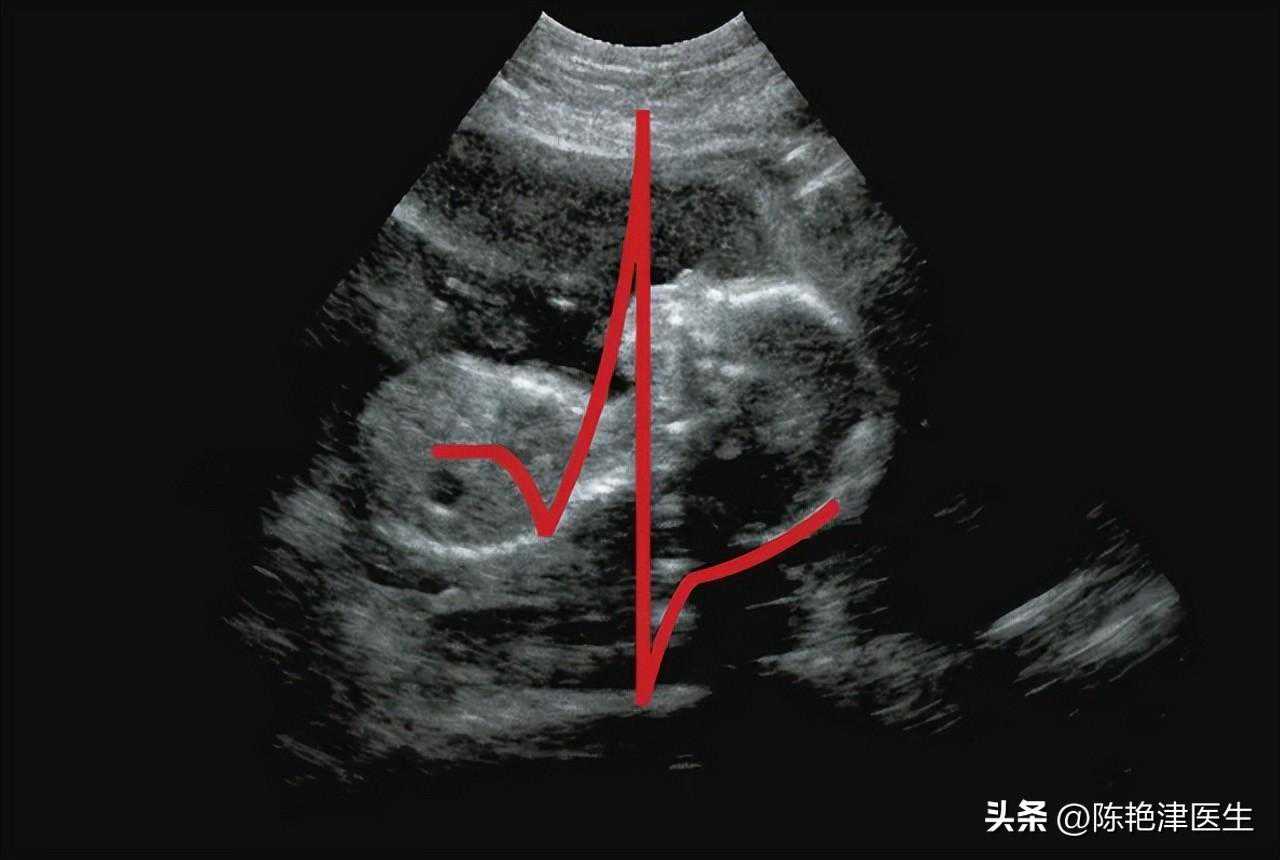

第三个检查:超声心动图

心电图和超声心动图都是诊断心脏功能的重要工具,但它们的工作原理和提供的信息各有侧重。超声心动图通过声波技术生成心脏图像,能够更深入地揭示心脏结构的细节,包括心脏瓣膜、心室和心房的大小及功能状况。

在心脏结构异常、心肌病和心脏瓣膜病等方面,超声心动图更胜一筹。

有些心脏疾病确实会导致心脏电活动的变化,但也有部分疾病仅影响心脏结构,而不影响心电表现。

例如,心脏扩大、收缩功能减弱或心脏瓣膜关闭不全,这类病变往往不会随着症状的缓解而自动改善,可以随时进行超声心动图检查以持续监测心脏状况。

心率加快时,超声心动图的具体表现可能因个体差异和潜在病因的差异而有所不同。在超声心动图的观察下通常表现为心脏的运动节奏显著增强。

由于心率加速,心脏的泵血功能也会相应提升,进而改变血流的动力学特性。在超声心动图的呈现中,这种变化可能直观地表现为血流速度的显著提升,有时甚至在特定情况下会出现血流的湍流或涡流现象。

此外,为了满足身体对血液需求的增加,心率加快时心脏每分钟输出的血量也可能有所增加。

相比其他检查项目,超声心动图技术具有诸多优势。它安全无创,不会对患者造成任何伤害;同时,其造价相对较低,使得更多患者能够负担得起这项检查。此外,超声心动图的结果可靠,床旁检查方便,可重复性高,因此备受临床医生的青睐。